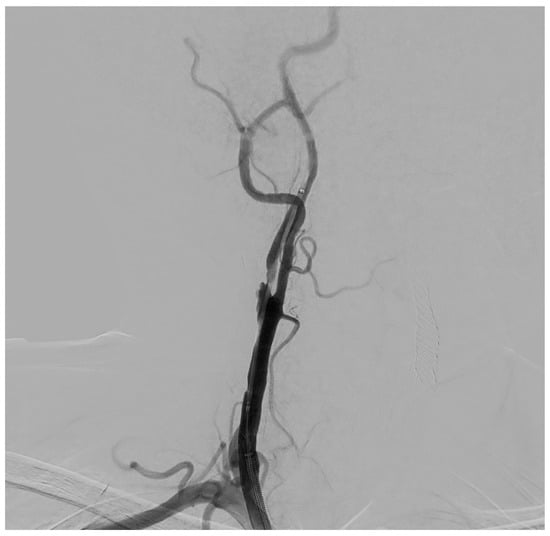

Figure 4. DSA showing a coaxial umbrella-like filter (Boston Scientific Filterwire Ez, 300 Boston Scientific Way Marlborough, MA 01752-1234), positioned in the distal ICA, to prevent embolic phenomena during the balloon angioplasty and stent positioning of the carotid stenotic plaque.

The procedure is performed in the angiographic suite, under mild sedation to monitor the neurological status of the patient, by arterial vascular access, usually femoral. With the wire–catheter system, the common carotid artery (CCA) of the pathological side is selectively catheterized and a diagnostic angiography is performed to identify the stenosed area (Figure 3). The stenosis carotid tract is crossed through the wire–catheter system, and only after the placement of a neuroprotection device in the ICA, a balloon angioplasty is performed to compress the atheromatic lesion and restore the original luminal vessel diameter. Regarding neuroprotection, today we have two classes of embolic protection devices available: a coaxial umbrella-like filter positioned in the distal ICA (Figure 4) or hemodynamic balloon block systems with reversal flow that can be placed either proximally or distally to the carotid stenosis with overlapping results in reducing the distal embolic phenomena risk but with a higher rate of periprocedural vasospasm in the case of a distal umbrella-like filter [53]. At this point, it is necessary to inject 1 mg of atropine to avoid vasospasm before releasing a permanent endovascular stent. We have three types of endovascular stents such as open-cell, closed-cell, or double-layer (Figure 5). Open-cell stents were worse than closed-cell due to the higher degree of plaque protrusion and the procoagulant state induced by the stent that can trigger embolic phenomena, recording a higher rate of stroke or restenosis at 30 days. The double-layer stents are still in the process of approval by the FDA although they have shown in some clinical trials strongly encouraging results with a risk of adverse events at 30 days <2% [54].